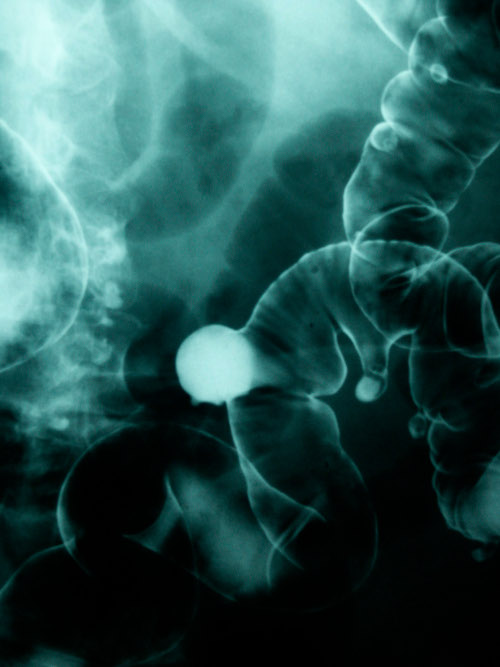

La zona dell’intestino più colpita è soprattutto quelle del retto, la parte finale del condotto intestinale, vicino all’ano, dove il tumore incorre nel 50% dei casi e nel tratto di colon denominato sigma, appena prima del condotto rettale, nel 20 % dei casi.